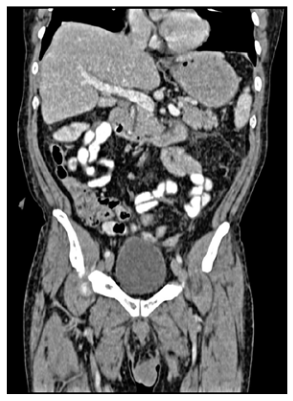

En el posoperatorio temprano, a los cinco días, se realizó una TAC toracoabdominal trifásica como parte de la estadificación adecuada, que mostró metástasis hepáticas en los segmentos III y VI, siendo la primera de 1 x 1 x 1.5 cm y la segunda de 4 x 3 x 2 cm. Estas lesiones no fueron visibles en la primera tomografía debido a que solo se realizó en fase simple, ni tampoco se identificaron a la palpación hepática durante la cirugía. (figuras 5 y 6).

Tomografía axial computarizada trifásica con metástasis hepática en el segmento VI

Tomografía computarizada trifásica corte coronal con metástasis hepática en el segmento III